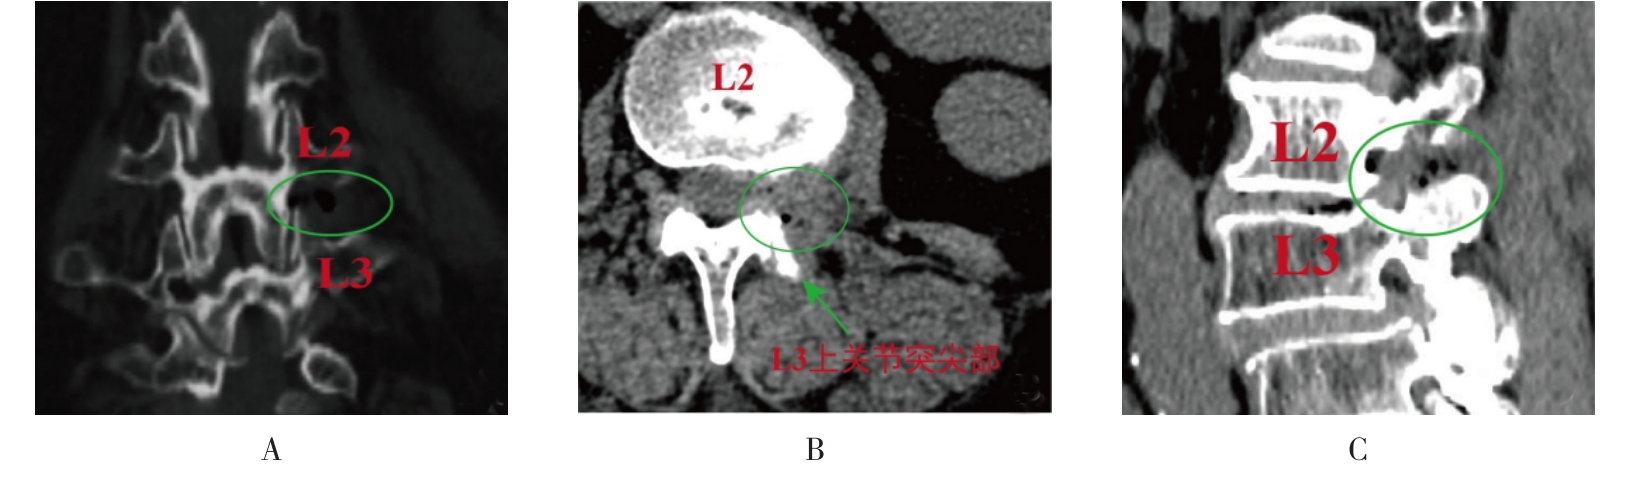

摘要:目的 观察单通道非同轴脊柱内镜经椎间孔外入路(椎板外切迹)治疗极外侧椎间盘突出症(FLLDH)的临床疗效。方法 回顾性分析2022年5月-2024年5月该院收治的,行单通道非同轴脊柱内镜经椎间孔外入路(椎板外切迹)治疗的FLLDH患者70例。于术前和术后,评估腰腿疼痛程度、腰椎功能和临床疗效。结果 相较于术前,术后3 d和3个月,患者下肢视觉模拟评分法(VAS)评分、腰部VAS评分、Oswestry功能障碍指数(ODI)、数字分级评分法(NRS)评分和Roland-Morris功能障碍问卷(RMDQ)评分明显降低,日本骨科协会(JOA)评分明显升高,差异均有统计学意义(P < 0.05);改良MacNab评分标准显示,末次随访时的优良率为94.28%。结论 单通道非同轴脊柱内镜经椎间孔外入路(椎板外切迹)治疗FLLDH,能明显改善患者腰腿疼痛和腰椎下肢功能,其具有创伤小、易操作、安全性高和疗效好等优点,值得在临床推广应用。